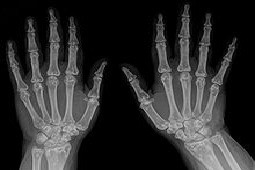

Reumatoidalne zapalenie stawów